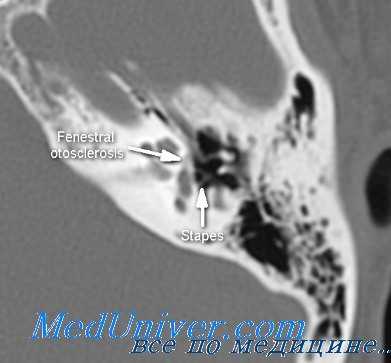

Отосклерозом называют патологический процесс, локализующийся преимущественно в лабиринтной стенке среднего уха около овального окна и заключающийся в лакунарном рассасывании компактной части стенки костного лабиринта и замещении ее спонгиозной пластинчатой костью. Этот процесс распространяется на кольцевидную связку окна преддверья и подножную пластинку стремени, в результате чего стремя замуровывается. Классическая форма отосклероза характеризуется ограничением подвижности стремени, в некоторых же случаях отмечается и полная его неподвижность (ankylosis stapedis).

Очаги отосклероза могут иметь множественный характер. В 50% случаев отосклероза их обнаруживают в области окна преддверия, в 35% — в капсуле улитки, в 15% — в полукружных канальцах. Расположение очага отосклероза в области окна преддверия приводит к вовлечению в склеротический процесс основания стремени с развитием его анкилоза. В результате возникающей обездвиженности стремени нарушается звукопроводящая функция уха и развивается кондуктивная тугоухость. Если очаги отосклероза находятся в лестнице лабиринта, то нарушается работа звуковоспринимающего аппарата уха, что ведет к появлению нейросенсорного типа тугоухости.

Происходящие при отосклерозе изменения костной ткани капсулы лабиринта иногда определяются по результатам прицельной рентгенографии черепа. Однако более информативным исследованием является КТ черепа, позволяющая визуализировать очаги отосклероза.

КТ височных костей. С обеих сторон диффузное снижение пневматизации ячеек сосцевидного отростка и пирамиды височной кости за счет отосклероза